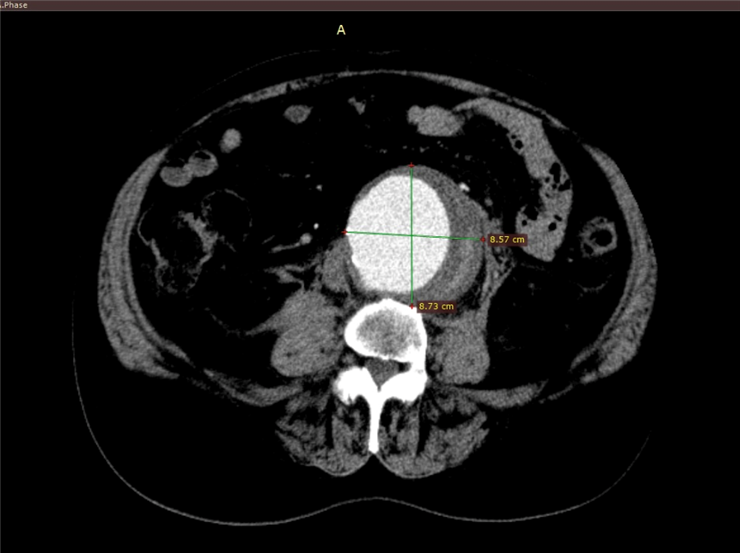

У місцеву лікарню він потрапив після появи різкого ниючого болю в нижній частині живота, а також в ділянці нирок й кульшових суглобів. Больові відчуття виникли раптово після прийняття гарячого душу. Під час проходження обстеження лікарі виявили аневризму черевного відділу аорти, у зв’язку з чим пацієнта було терміново направлено до Центру хірургії та трансплантології ім. О.О. Шалімова.

Після повторного КТ дослідження в нашому Центрі було діагностовано, що аневризма досягла критичних розмірів понад 10 см, відбувся розрив задньої стінки. Це спричинило виникнення крупної заочеревинної гематоми, що становило безпосередню загрозу життю хворого. Пацієнта було оперативно прооперовано командою судинних хірургів – виконано резекцію аневризми черевної частини аорти та лінійне алопротезування аорти.